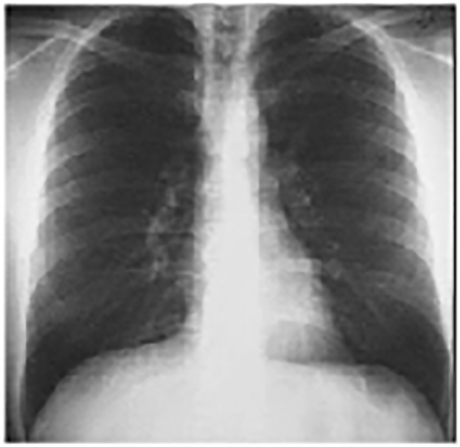

PA and Lateral

These chest X rays are normal. The PA view demonstrates no abnormalities of the bone structures, lung fields, or cardiac silhouette. The right and left heart borders are normal as are the great vessels superior to the cardiac silhouette. Note the cardiothoracic ratio is also normal, that is, it is less than 50%.